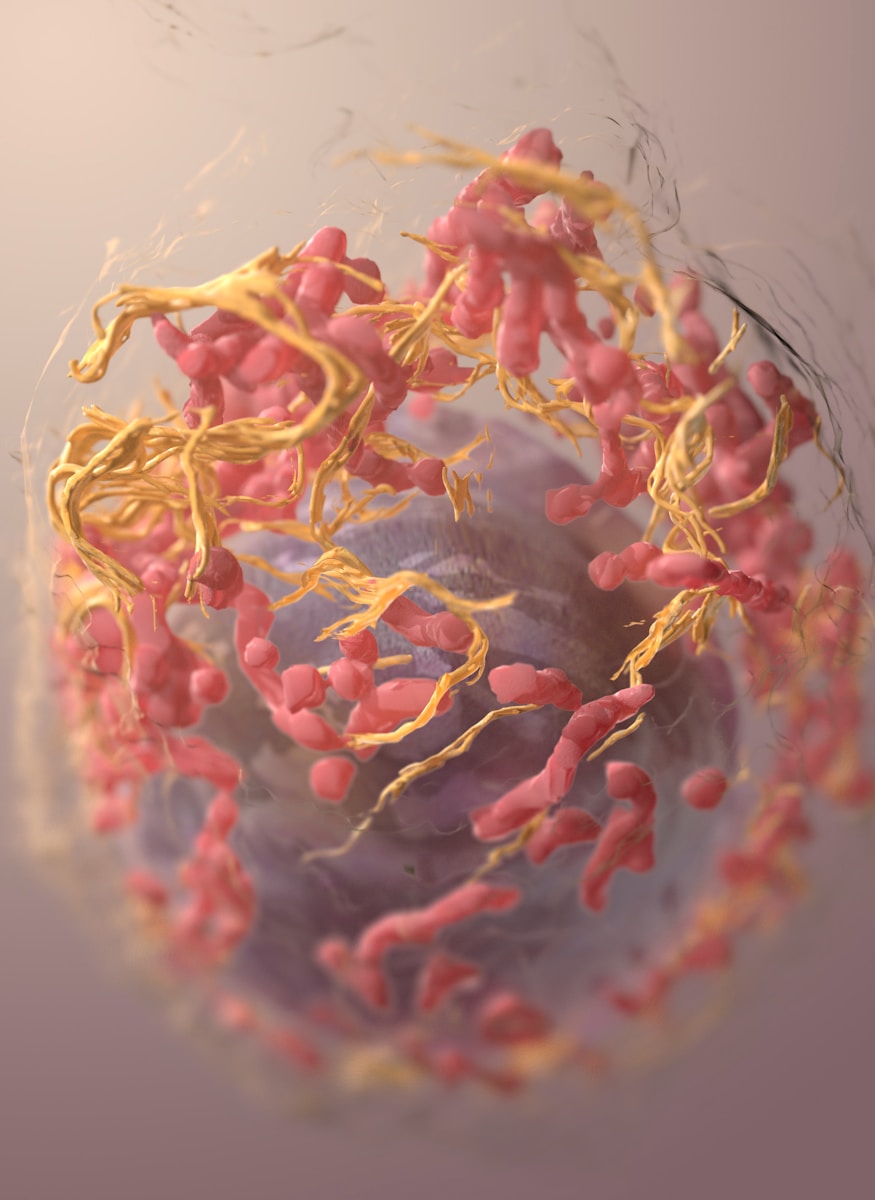

8. Imunitný systém bojuje s rakovinou každý deň

Naše telo denne rozpoznáva a ničí rakovinové bunky, často skôr, než si to vôbec uvedomíme. Imunitný systém má schopnosť zastaviť ich rast, no stačí, aby sa jednej nebezpečnej bunke podarilo uniknúť kontrole a môže vzniknúť nádor.